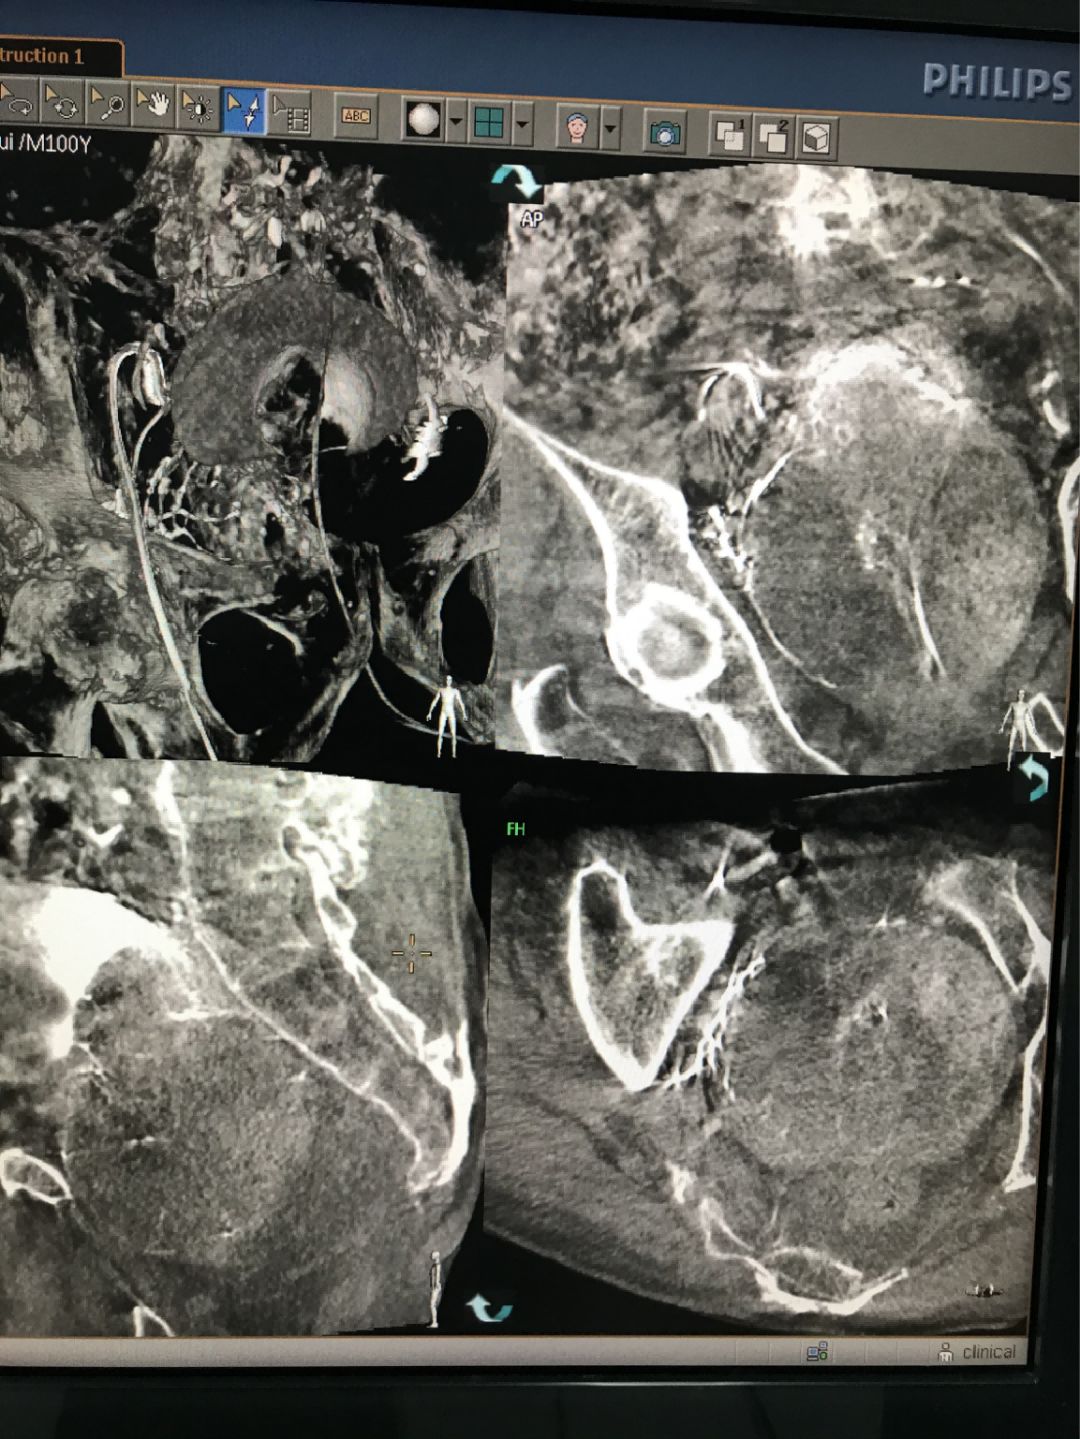

圖:使用CBCT掃描避免誤栓其他血管